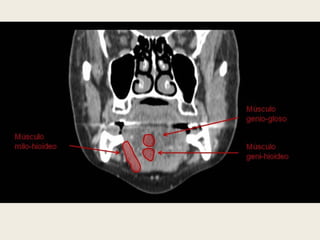

EL CUELLO SUPRAHIOIDEO

 El cuello suprahioideo

comprende desde la base del

cráneo hasta el hioides,

incluyendo toda la porción

extracraneal a excepción de

las órbitas, la cavidad oral y

los senos paranasales.